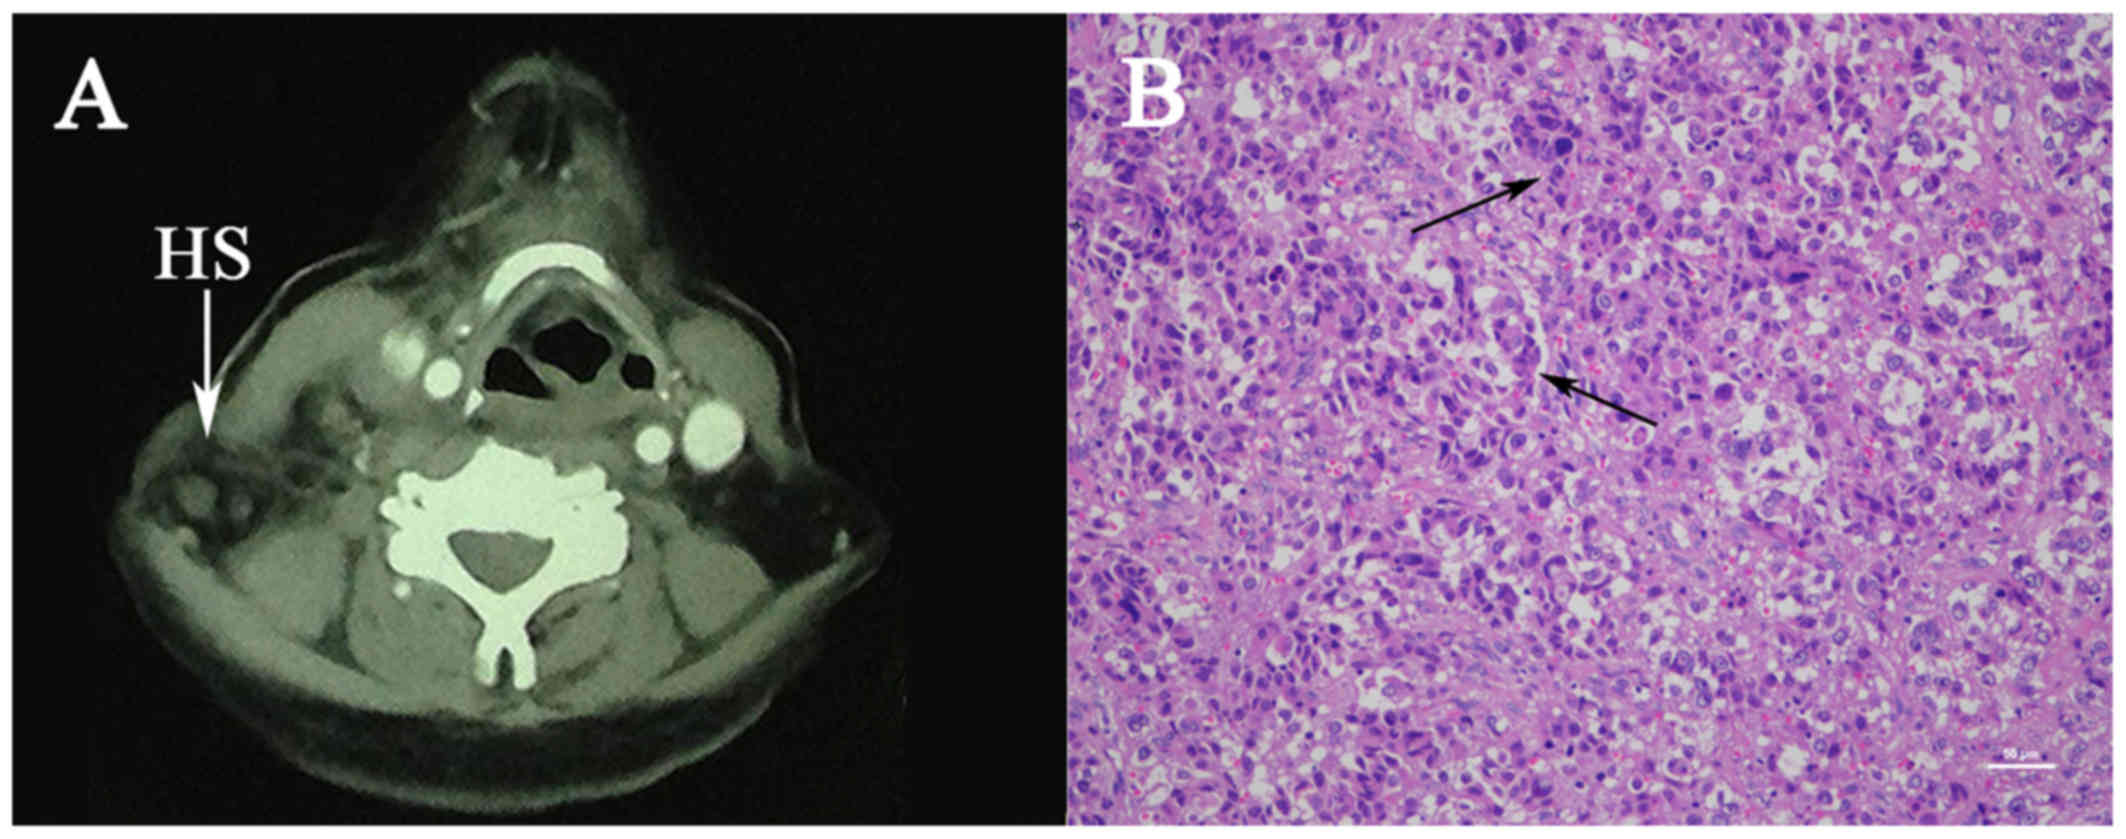

The mean overall survival during the study period was 541 months. Histiocytic sarcoma HS is an extremely rare non-Langerhans histiocyte disorder of unknown cause that most commonly presents with symptoms due to unifocal or multifocal extranodal tumors.

Histiocytic Sarcoma Of The Neck A Case Report